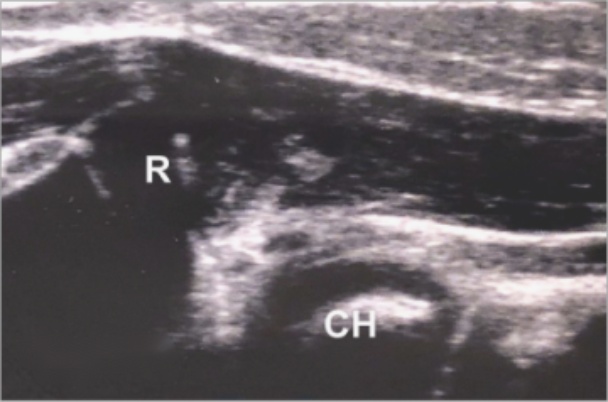

还可以在前臂旋后位肱桡关节外侧冠状位纵切面观察桡骨头和肱骨小头的位置关系。在正常儿童肘关节的超声图像上,可以见到两个圆形的低回声隆起,我们将其称为“双峰征”(见图2(a))。肱桡关节对线正确的第二个标志是桡骨(凹面)和肱骨(凸面)的相应关节面处于同一平面上(见图2(b)箭头处),我们将其称为“一致性[9]”。在肱桡关节外侧冠状位纵切面的异常声像中,桡骨头与肱骨的正常位置关系丢失,两种征象均不可见(见图2(c)),此可作为环状韧带卡压进入肱桡关节的提示。

(a) (b) (c)

Figure 2. Sonographic findings of the lateral coronal longitudinal section

2. 外侧冠状位纵切面超声表现